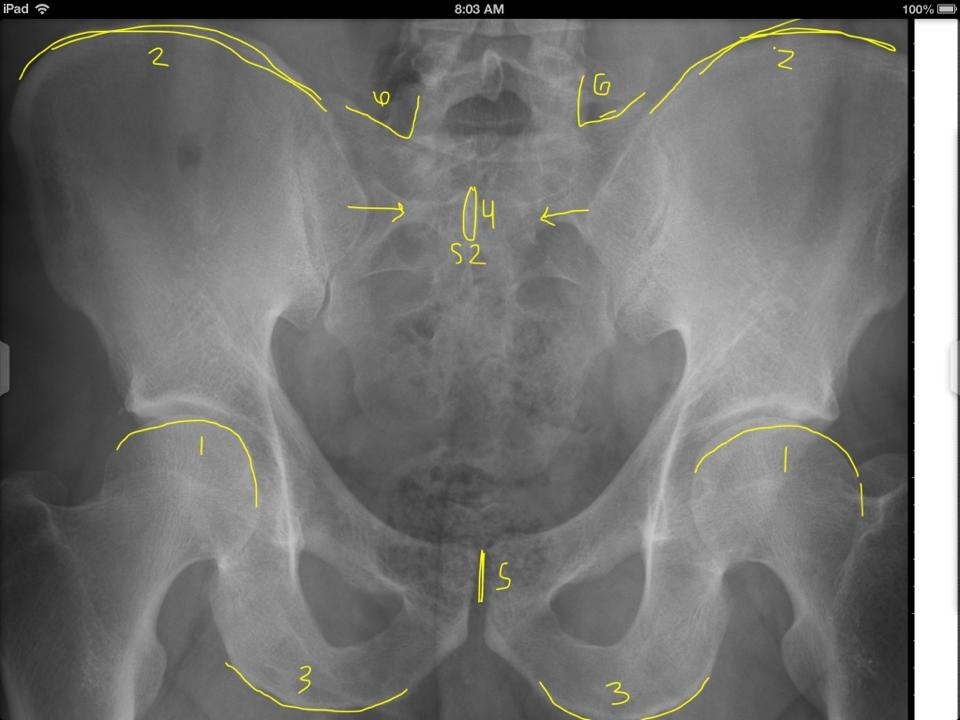

Superior aspect of femur heads

Superior aspects of iliac crest

Inferior aspect of ischial tuberosities

S2 tubercle

Pubic symphysis

Sacral Grooves